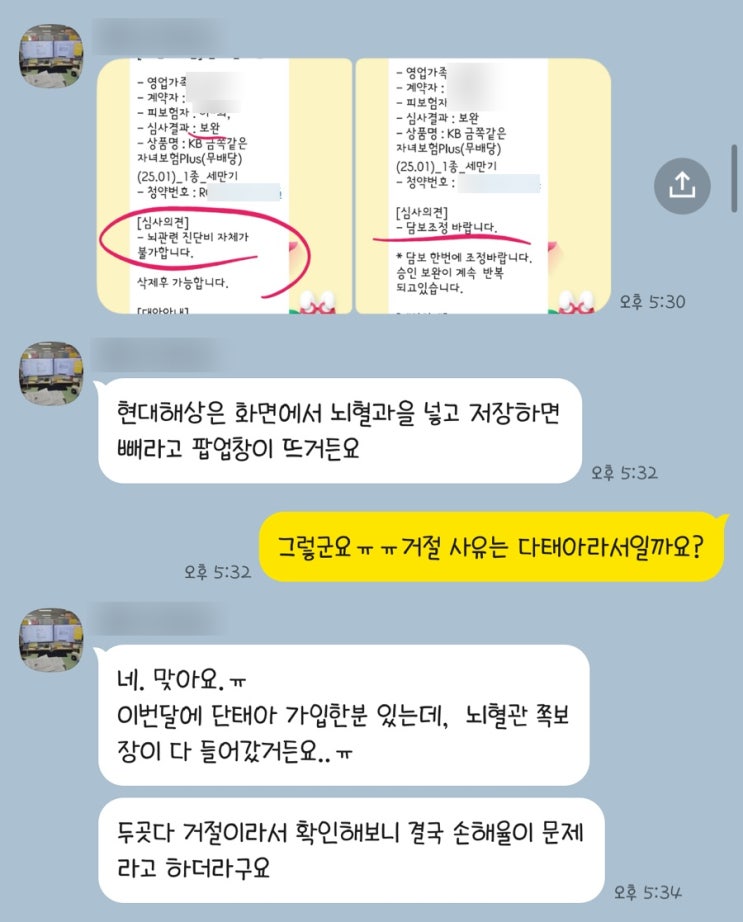

21~22주 쌍둥이 태아보험 가입 후기(+꿀팁, 가입시기, 불필요한 특약)

21주 목주름이 너무 많이 생겼다ㅜㅜ 배는 점점 불러오는데 위도 불편해서 계속 높은 베개를 배고 잔 탓일...